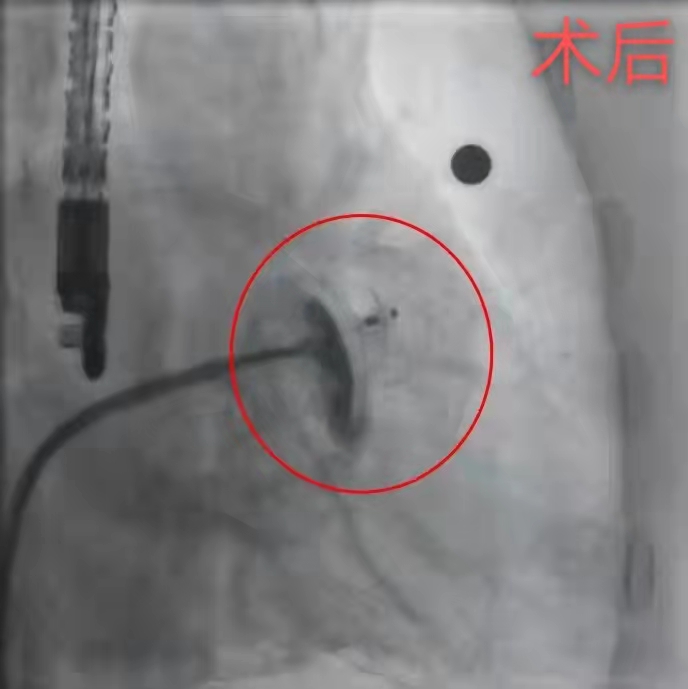

封堵术后造影显示左心耳内无分流